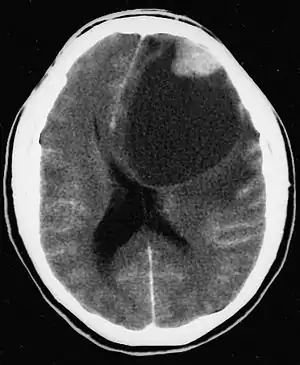

| CT scan of a brain with pleomorphic xanthoastrocytoma. The classic radiographic appearance is one of a superficially situated tumor, here a mural nodule, associated with an underlying cyst. | |

Pleomorphic xanthoastrocytoma usually develops within the supratentorial region (the area of the brain located above the tentorium cerebelli). It is generally located superficially (in the uppermost sections) in the cerebral hemispheres and involves the leptomeninges. It rarely arises from the spinal cord.

These tumors are formed through the mitosis of astrocytes. They are found in the area of the temples, in the brain's frontal lobe or on top of the parietal lobe. In about 20% of cases, tumors exist in more than one lobe.